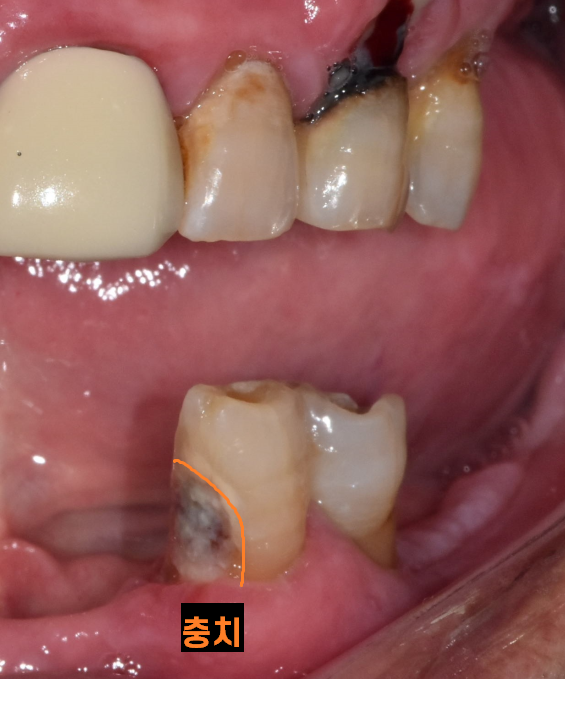

아래 치아를 볼까요?

230725

튼튼한 턱뼈를 가진 아래 치아는 그나마 상태가 양호하네요.

충치 치료를 통해

최대한 살려보아야겠습니다.

아래 치아가 이렇게 많이 썩었는데..

안아프시답니다.